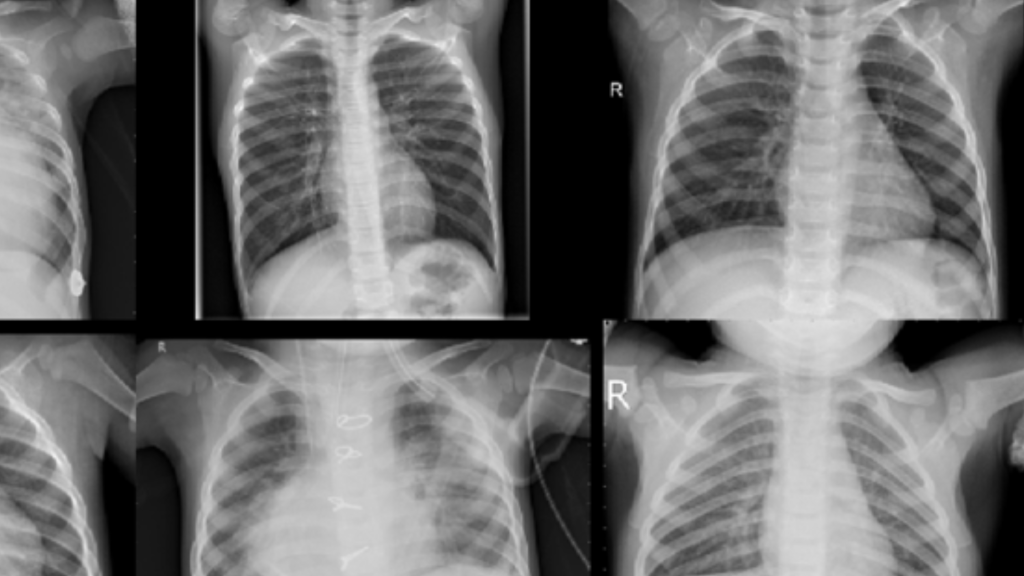

Kursus Jasa Skripsi Tesis Disertasi MATLAB ~ “Pengembangan Model Pembelajaran Mesin Berbasis MATLAB untuk Diagnosis Penyakit Menggunakan Citra Medis”

Berikut adalah silabus 20 sesi untuk kursus “Pengembangan Model Pembelajaran Mesin Berbasis MATLAB untuk Diagnosis Penyakit Menggunakan Citra Medis”: Sesi 1: Pengenalan MATLAB dan Citra Medis Tujuan: Memahami dasar-dasar penggunaan MATLAB untuk pengolahan citra medis. Materi: Instalasi dan konfigurasi MATLAB. Pengenalan MATLAB untuk pengolahan citra. Format citra medis (DICOM, PNG, JPEG). Pengantar pemrograman MATLAB. Sesi … Lanjutkan membaca Kursus Jasa Skripsi Tesis Disertasi MATLAB ~ “Pengembangan Model Pembelajaran Mesin Berbasis MATLAB untuk Diagnosis Penyakit Menggunakan Citra Medis”